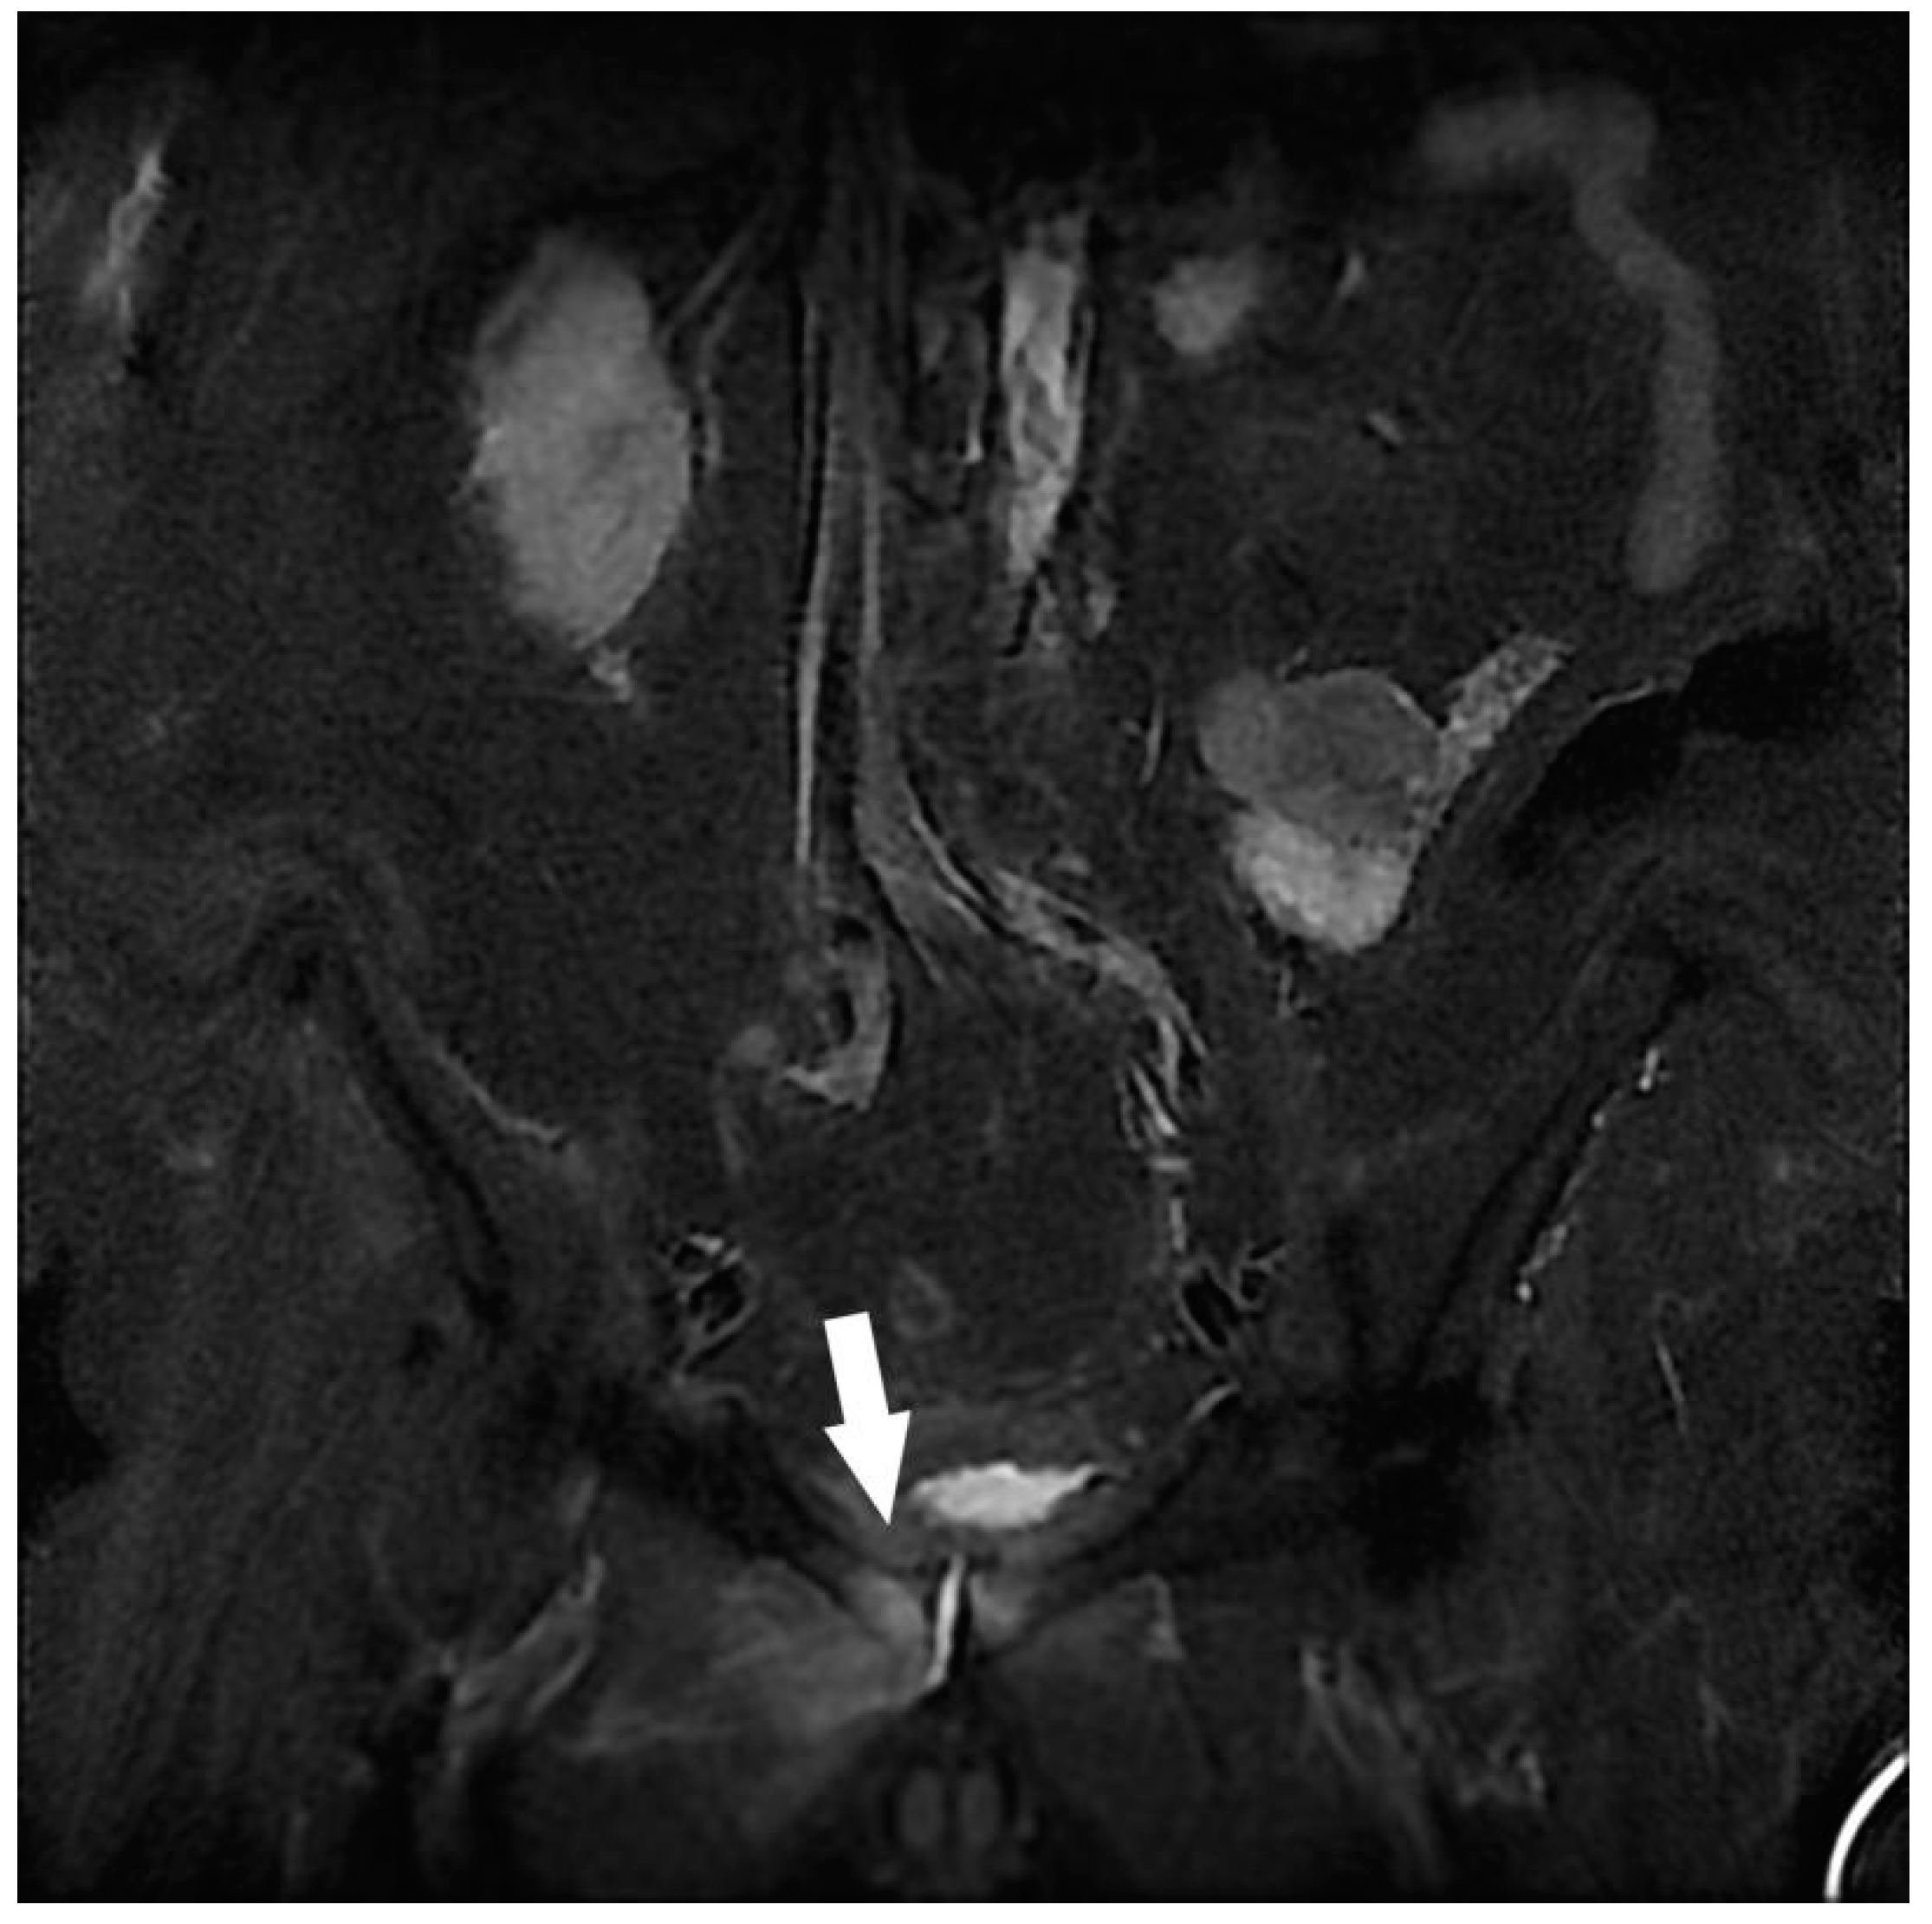

| Others | Endometrioma with posterior deep pelvic endometriosis | 1 |

| Ischio-femoral impingement | 1 | |

| Retroperitoneal mass syndrome with urinary obstruction | 1 |

| Indeterminate pelvic mass 1 | 1 | |

| Diffuse uterine adenomyosis | 1 | |